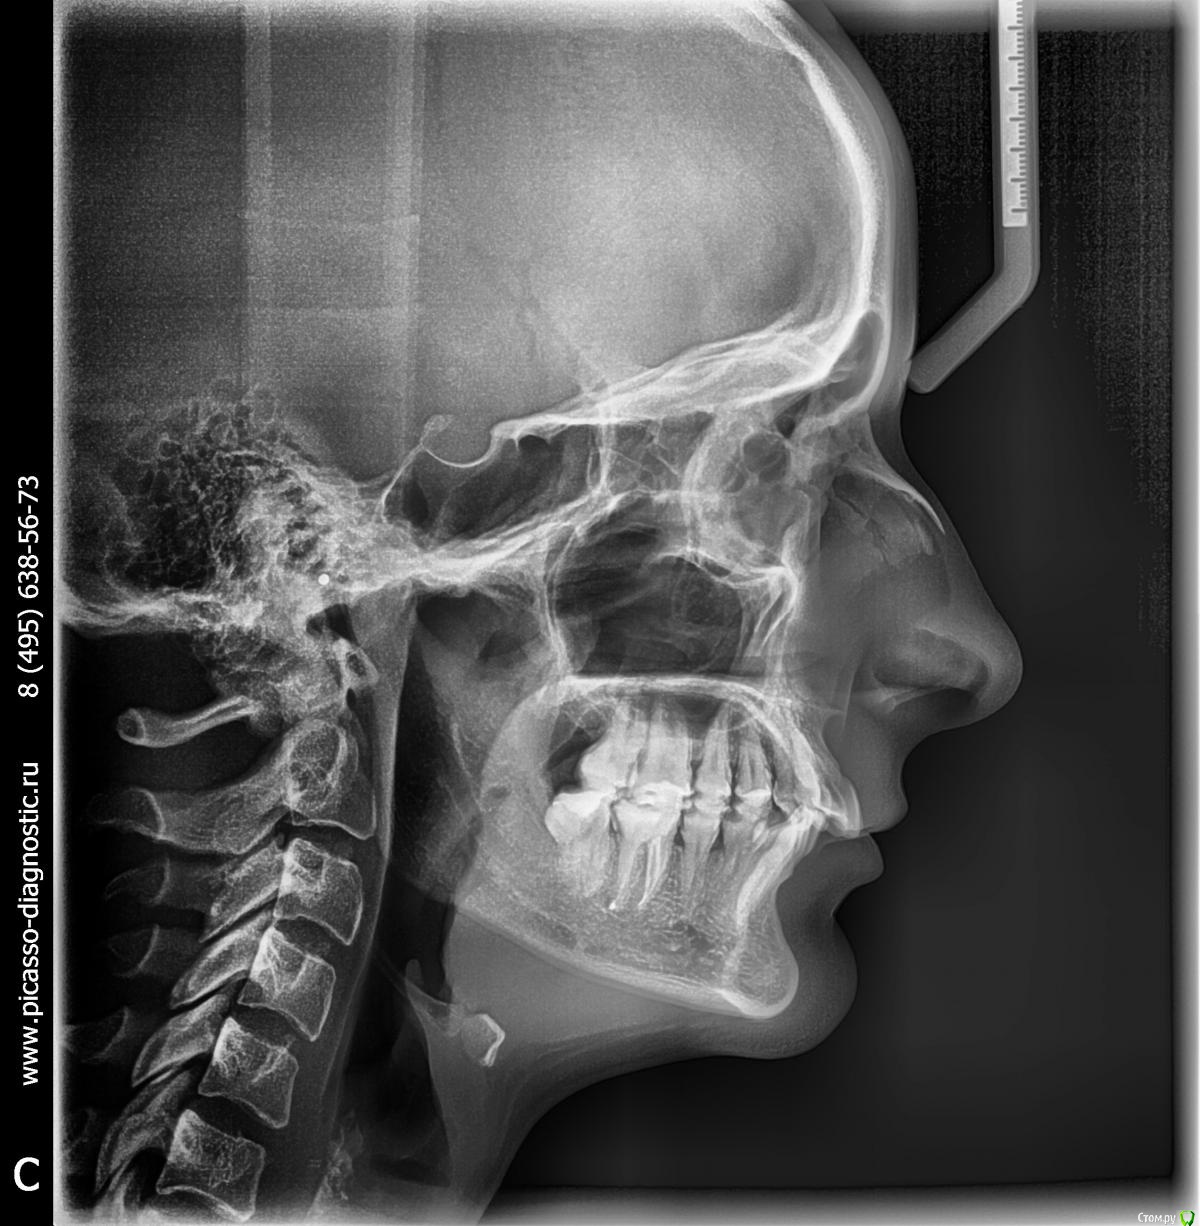

Екатерина556 Опубликовано 16 августа, 2015 Поделиться Опубликовано 16 августа, 2015 Добрый день! Обращаюсь с просьбой о консультации, а также может быть кто-то сможет посоветовать лечащего врача.В детстве носила брекеты, однако после того как их сняла и начали расти 8-ки зубы опять сдвинулись. На текущий момент все восьмерки удалены и хочу понять целесообразность еще раз проходить через брекеты. Лечащий врач сказал, что без удаления зубов в моем случае ничего не получится. Хотела бы понять действительно ли это так? И вообще в моем случае насколько возможно сделать все качественно, чтобы потом ничего никуда не разъехалось. Также большая просьба посоветовать компетентного врача, которым мог бы помочь с данной проблемой.Снимки прилагаюг. Москва Ссылка на комментарий

Екатерина556 Опубликовано 22 августа, 2015 Автор Поделиться Опубликовано 22 августа, 2015 Фотографии Ссылка на комментарий